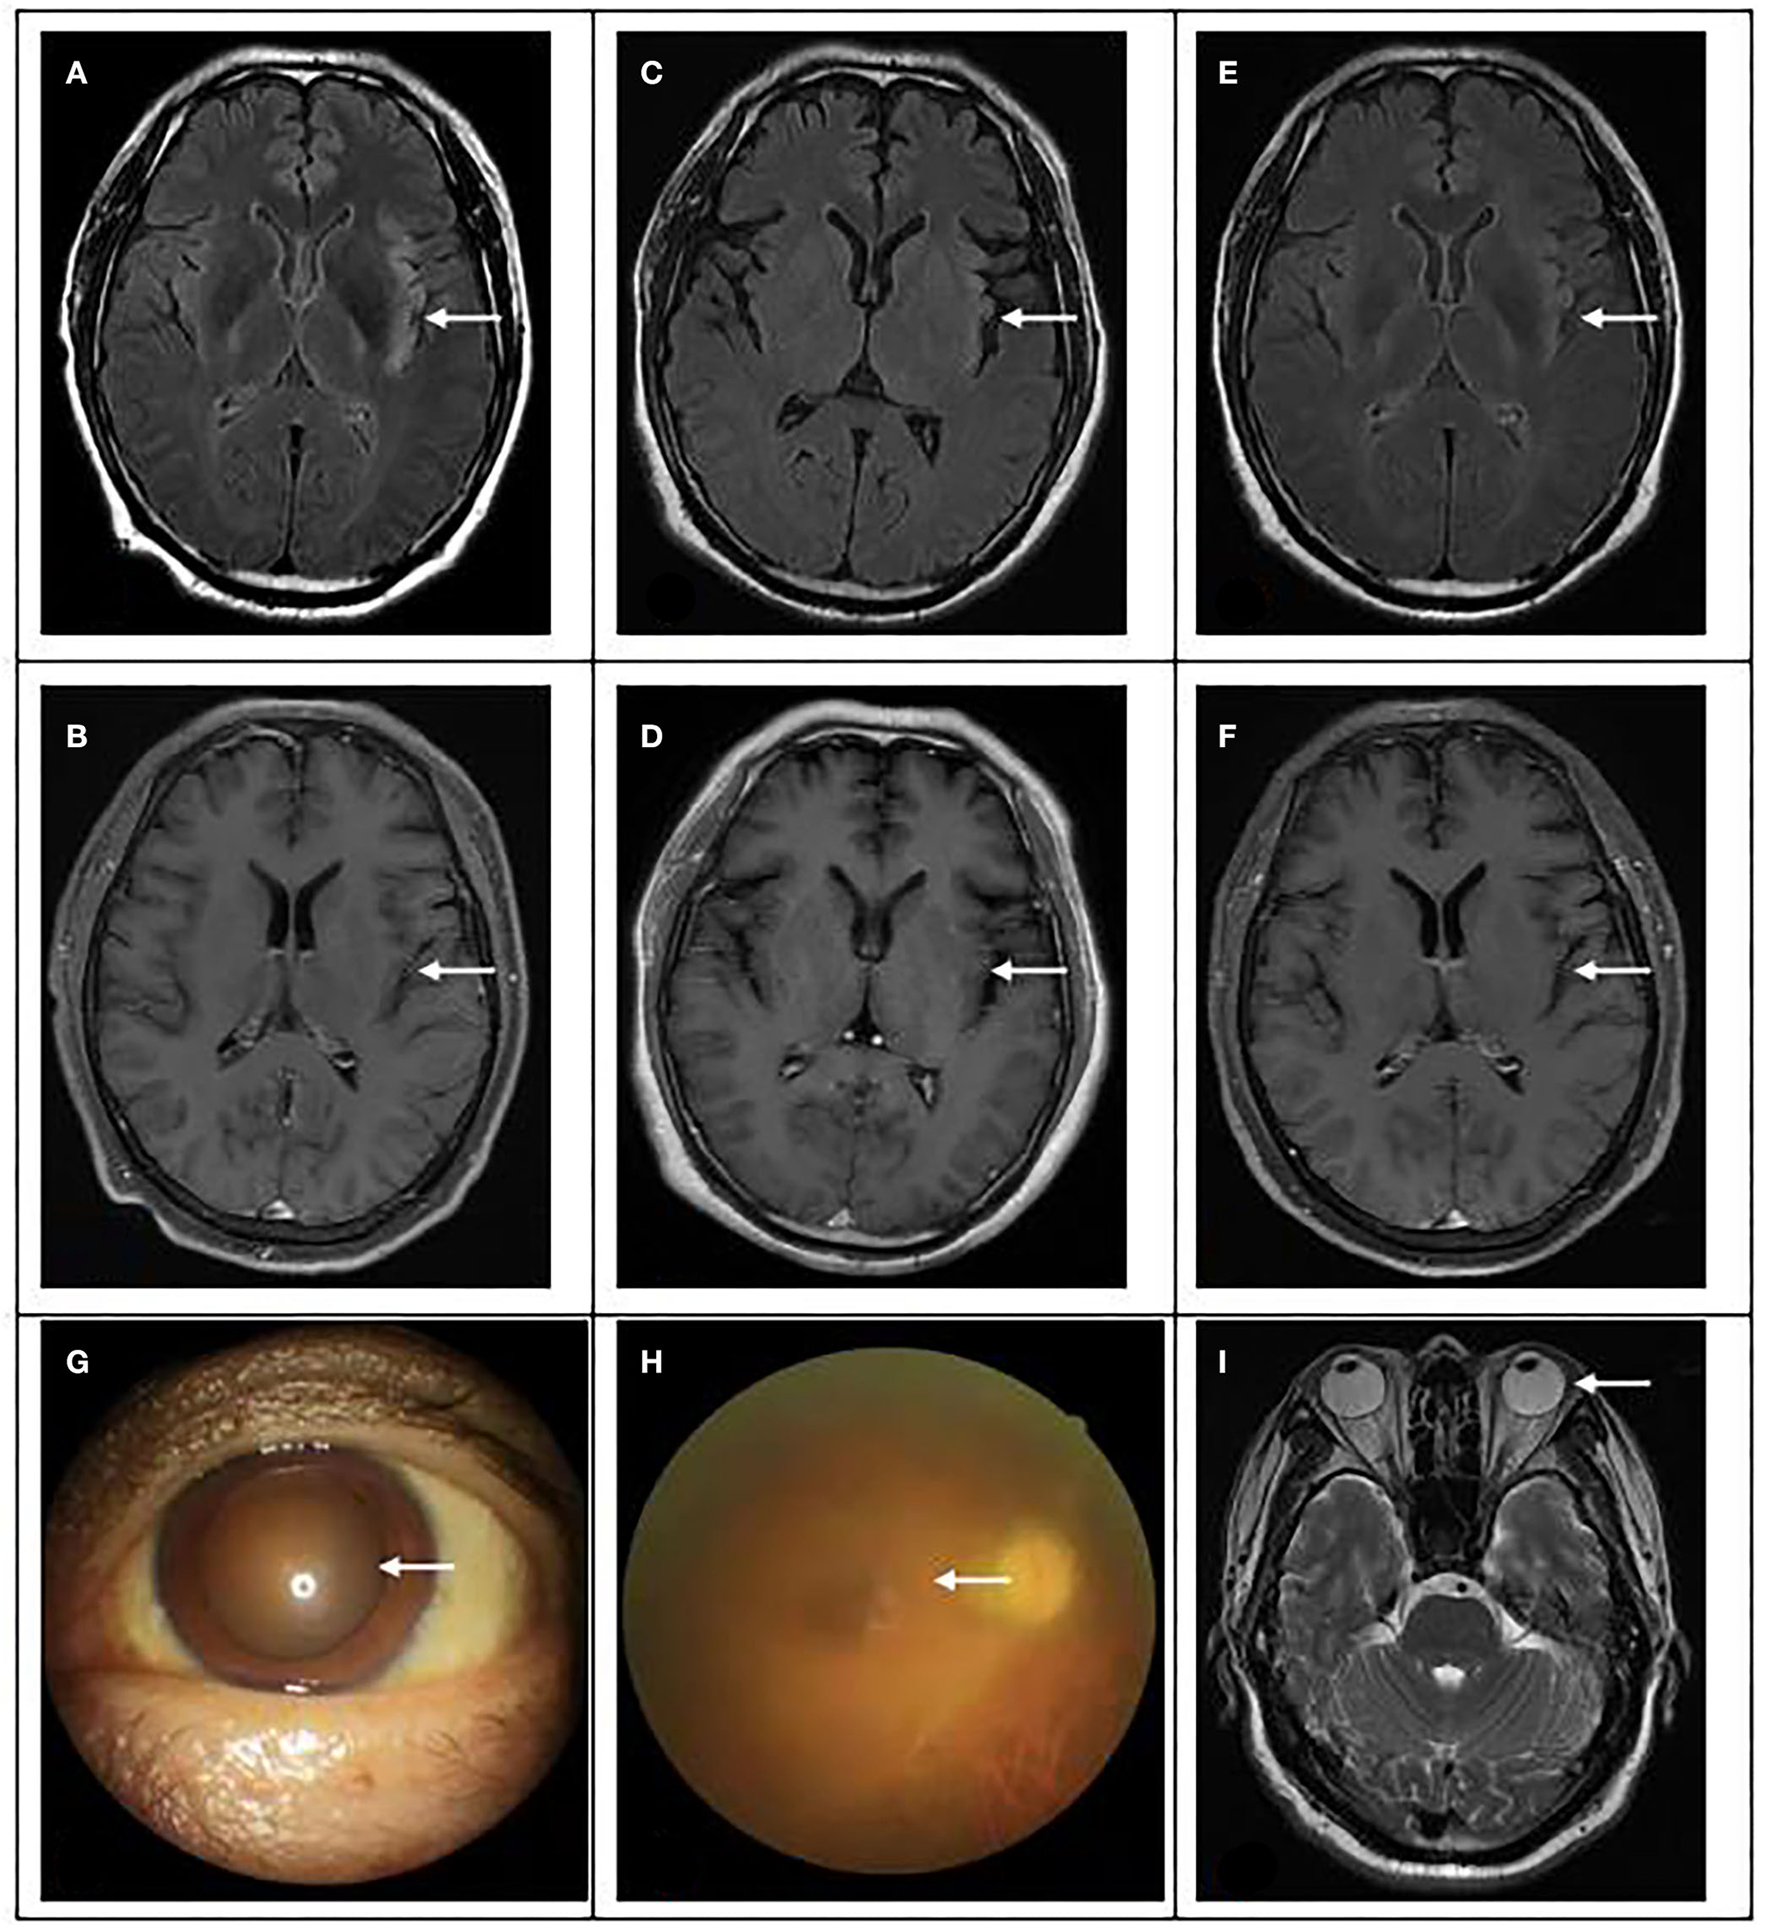

Brain magnetic resonance and eye examination results. (A,B) On 15 April, brain magnetic resonance showed multiple spots and bands of abnormal signals in the left insular and temporal cortex, high signal in T2WI and T2flair, and equal and low signal in T1flair. (C,D) On 24 April, MRI showed abnormal signal and meningeal changes in the left frontal temporal insula. (E,F) On 04 June, magnetic resonance imaging showed that the range of inflammatory lesions was slightly smaller than before. (G) The pupil of the patient was significantly enlarged, with a diameter of 5 × 5 mm. (H) Fundus lesions: vitreous cavity is turbid, the optic disc boundary is indistinctly seen, and white line changes can be seen in the peripheral momentum. (I): No abnormality was found in eyeball magnetic resonance.

Improve related examinations, blood routine: WBC 8.7 g/L, NE 76.4%, HGB 163 g/L, PLT 111 G/L, blood biochemistry: TBil 53.4 umol/L, NCBil 43.3 umol/L, SAA 21.4 mg/L. There were no abnormalities in the electrolyte, liver function, renal function, blood glucose, high-sensitivity C-reactive protein, erythrocyte sedimentation rate and coagulation function, as shown in Table 1. Electroencephalogram (EEG): the main rhythm of each lead was 10 HZα with medium and low amplitude, and the parietal and occipital region was dominant, with left and right asymmetry and poor amplitude modulation. The left lead had more rhythm and activity of 4–7 HZθ with medium and low amplitude, and slightly more activity of 3–3.5 HZδ, and the front head was very biased. Brain magnetic resonance imaging (MRI): multiple spots and bands of abnormal signals were found in the left insula and temporal cortex, T2WI and T2 flair showed hyperintensity, T1 flair showed isointensity and hypointensity, and GD-DTPA enhanced scanning showed no obvious abnormal enhancement, as shown in Figure 1. Cranial MRA, MRV, neck vascular color ultrasound, chest CT, electrocardiogram, and heart color ultrasound showed no abnormalities. The patients were treated with epilepsy control, brain edema prevention, brain cell nutrition, anti-infection, water and electrolyte balance and liver protection, and closely monitor the changes of vital signs and mental pupils.

On 19 April, the patient became drowsy. After people shouted, he could open his eyes and move according to the instructions. He still had an intermittent fever, the highest temperature was 38.6°C, there was no headache, the activity of the left limb was normal, the muscle strength of the right limb was grade 3, and there was no limb convulsion. Spontaneous breathing had been restored and the ventilator had been evacuated, but it is still in the state of endotracheal intubation. The second generation sequencing results of cerebrospinal fluid showed that it was infected with pseudorabies virus with a coverage rate of 1.86%, see Figure 2 for details. There was no abnormality in the second-generation sequencing of serum, and the antibodies of cerebrospinal fluid and serum to autoimmune encephalitis were negative. After inquiring about the medical history, we learned that the patient had been engaged in the pig industry for a long time. The patient had a clear diagnosis of viral encephalitis and continues to receive antiviral treatment. Considering that some of the patients were prone to retinitis leading to blindness, we invited ophthalmology to consult. Eye ophthalmologist examination: there was no congestion in the conjunctiva, the cornea was transparent, and the pupils of both eyes were very small, about 1.5 × 1 5 mm, direct and indirect light reflection existed, and it was difficult to peep into the fundus through ophthalmoscopy. On 22 April, the lumbar puncture was rechecked, the pressure was 220 mm water column, the routine and biochemical results of cerebrospinal fluid were not significantly changed. On 24 April, the patient's mind improved, the activity of the right limb was still poor, and the pupils on both sides were equal round, with a diameter of 3 mm. Re-examination of cranial MRI showed that the left frontotemporal insula had abnormal signals and meningeal changes, and the possibility of inflammatory lesions was high, which was better than before. On 27 April, the patient still had fever, the highest body temperature was 37.8°C, and the right muscle strength was grade 3. After pulling out the endotracheal intubation, the respiration was steady.

On 29 April, the patient could speak clearly, but the speech did not accord with the scene, and he was restless intermittently. Physical examination showed that memory and calculation ability were decreased, bilateral pupils were equal in size and circle, 5 mm in diameter, right muscle strength was grade 4, Risperidone was added for symptomatic treatment, and the rest remained unchanged. Therefore, we asked for ophthalmic consultation. Ophthalmic examination: VOD: 0.25, VOS: finger/2.5 m, fixed pupils in both eyes, mydriasis, 5 × 5 mm, fundoscopy showed that the retina at the posterior pole was flattened, no obvious hemorrhage or exudation was found. Therapeutically, antiviral eye drops and other local treatments were administered locally.

On 04 May, the patient was conscious, without irritability, and the muscle strength of the right limb was further improved, but the vision was still unclear. After reexamination of lumbar puncture, the cerebrospinal fluid pressure was 140 mm water column, the protein content increased, and there was no significant change in the rest. On 5 May, invited ophthalmology to consult again. Ophthalmic examination: VOD: 0.1 (+ 4.75d / + 1.25d × 155 corrections no response), VOS: 0.1 (+ 5.00d / + 1.50D × 180 corrections no response); Intraocular pressure: od 14 mmHg, os 14 mmHg; There was no congestion in the conjunctiva of both eyes, the cornea was transparent, the anterior chamber was deep, the crystal was transparent, the pupils of both eyes were fixed and dilated, 5 × 5 mm, the pupil margin was adhered to the front surface of the lens, pigmented keratic precipitates (KP) could be seen in the pupil area, fundus: vitreous cavity was turbid, the boundary of the optic disc could be seen faintly, and white linear changes could be seen in the peripheral omentum; The right eye macular OCT showed that the morphology of the right eye fovea was recognizable, the inner surface of the macular retina was still smooth, and the local ellipsoid structure was slightly disordered, see Figure 2 for details. The OCT of the left eye macular did not cooperate. B-ultrasound showed vitreous opacity in both eyes. It is necessary to continue to give eye drops to the patient for treatment.

On 12 May, the patient complained of transient dizziness when he got up and moving, which disappeared after standing. Both eyes were still blurred, bilateral pupils were dilated to the edge, the light reflex disappeared. The patient asked to be transferred to a superior hospital for treatment. On 3 June, the patient came to the hospital for follow-up visit, and the pathological changes in both eyes were no better than before. Reexamination of MRI showed that the range of inflammatory lesions was slightly smaller than before.